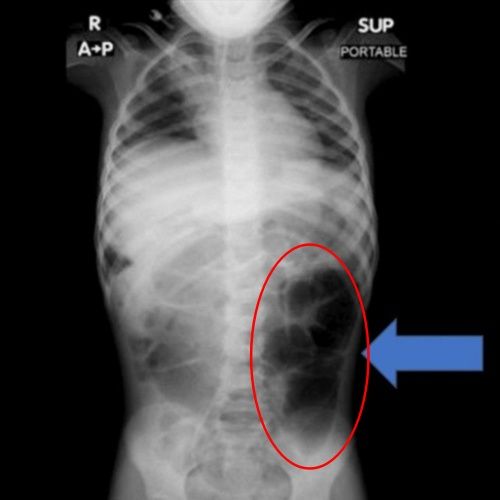

23일 의학 저널 '큐레우스'에 따르면 최근 사우디아라비아에 사는 6살 여아 A양은 복통과 소화 장애 증상이 지속되자 병원에 방문해 정밀 검사를 받게 됐다.

ⓒ큐레우스검사 결과 A양의 위 내부에서는 비정상적으로 큰 이물질이 발견됐으며,의료진은 수술을 통해 이를 제거했다.해당 이물질은 다량의 머리카락이 엉켜 형성된 덩어리로,위에 머무는 데 그치지 않고 소장의 일부까지 길게 이어진 상태였던 것으로 확인됐다.

의료진은 "소아 환자에게 반복적인 복통이나 구토,브라우저 게임식욕 저하 증상이 장기간 지속될 경우 위장관 내 이물질 가능성을 염두에 둬야 한다"며 "영상 검사를 통한 조기 진단과 신속한 치료가 중요하다"고 설명했다.